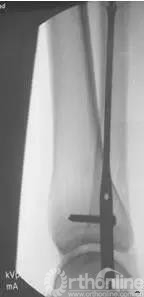

正侧位透视,髓内钉位置满意

术后侧位片